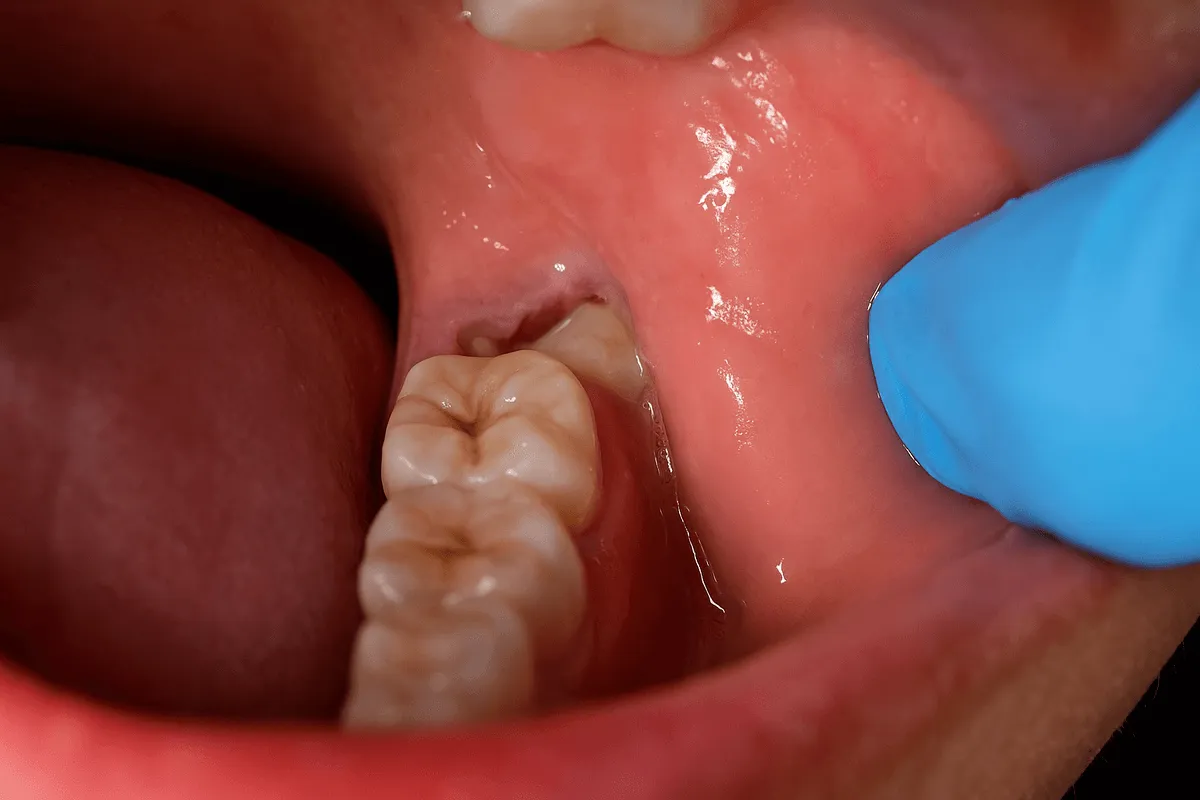

Din acest motiv, foarte multe măsele de minte rămân parțial sau complet incluse în os, erup strâmb sau exercită presiune asupra molarilor doi.

Cele mai comune indicații sunt: erupția incompletă cu pericoronarită, caria măselei de minte sau a dintelui vecin, poziția orizontală sau oblică, inflamații recurente, chisturi asociate sau necesitatea tratamentului ortodontic.

Este necesară pentru măselele incluse sau semiincluse. Presupune incizie gingivală și, uneori, secționarea dintelui.